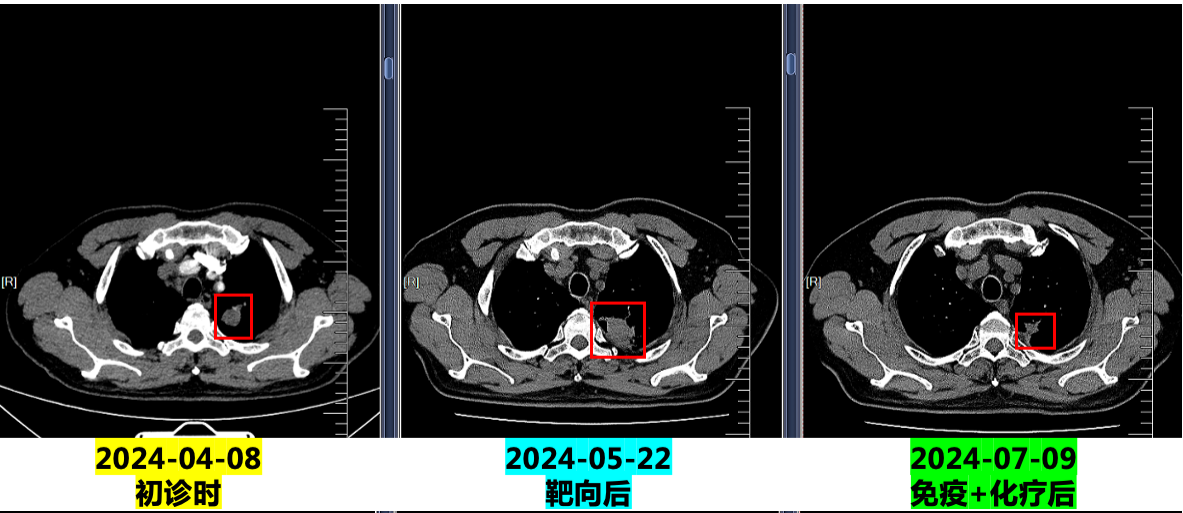

2.2024.5.22复查:咯血增多,胸部CT示病灶明显增大,评估疾病PD,停用特泊替尼。

3. 2024.5.27:予培美曲塞+卡铂化疗,出现皮疹(口服氯雷他定片后4-5天消退)。

4. 2024.6.17至今:行培美曲塞二钠0.8g + 卡铂400mg + 舒格利单抗1200mg(共20程,维持治疗中,无不良反应)。

临床随访影像对比